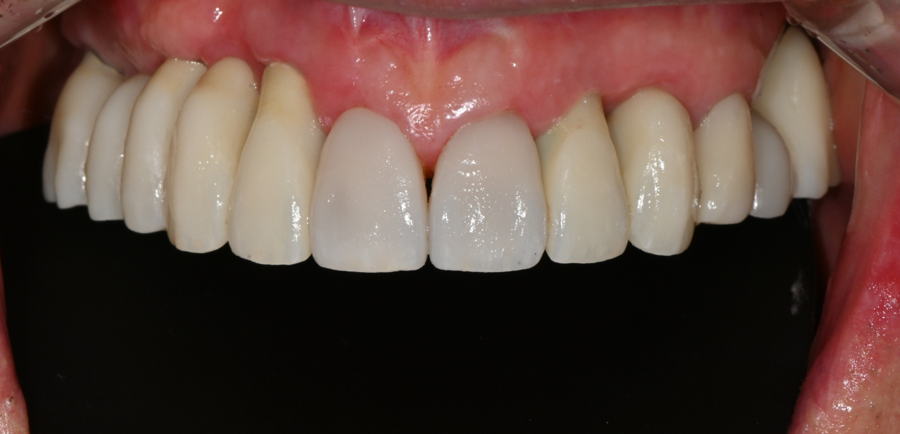

Final OVZERO veneer placement (OVZERO)

The final veneers completed in the lab were made with a subtle translucency like natural light,

a texture close to natural teeth,

and a shape that naturally matched the senior patient’s lip line.

After placement, the patient looked in the mirror

and smiled brightly, saying,

“I think I look 10 years younger.”

In particular, once the front teeth became brighter,

the entire face took on a softer and brighter impression.